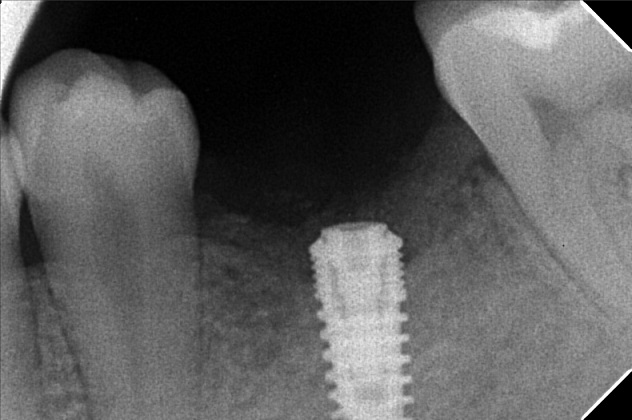

Edit Record Check our patient data records. Add patient information Patient Info Profile picture Last Name First Name Middle Name Birthdate Age Street Barangay City Country Zip Code Contact number Email Procedure 01/16/20 #18 niti lower #41 RW (distal) 09/17/21- exo 16/ upper for removal lower teeth- 34^ 16*16ssL 4/21/22- Implant #16 4.3 x 10mm with sinus lift #36 4x3 x 10mm under Iv CS 09/06/22 peri implantitis/ currettage and debridement/ ozone/ CGC/PRF/ bone filler- bio oss 025g 10/5/22 - CHECK UP; PRESCRIBED VIT D 1000IU; 0.9%NSS; ORAHEX 11/04/22-2healing Ab. 12/13/22- Pick up impression 12/24/22- IntsofCrown 5/06/23- Odontectomy tooth #12/Compound odontoma removal GBR-double oss cancellous and cortical bone 1cc and .25 cc with xenograft .25g/PRF-GTR Trapezoidal flap under IV conscious sedation non resorbable suture-nylon Specimen histopathology 05/20/23- removal of suture/ozone therapy/LC 46 mesial, Occlusal, buccal removal of amalgan 46 06/29/23- check up/xray/rem bal 3200 08/25/23-#12 Build Up/ Lingual retainer/OP 3200 BALANCE USED 04/19/24 check up LC #36 Occlusal of crown #26 lingual pit 05/25/24 3D scanning 10/04/24 #12 4mmx 11.5mm w/ incidental graft 1CGF 3 PRF membrane Odontectomy #38 10/12/24 attachment of temporary teeth 03/14/25 install healing abutment OP 05/01/25 3D scanning #12 full contour top abutment O/D: 5 G/H: 3MM A/H: 8MM 01/31/26 LC#37-B OP w/polish File micheal_2.jpg File 2 micheal.jpg File 3 img_20220421_171028.jpg File 4 300391815_794848065019598_3764074978376967115_n.jpg File 5 301522684_1451524321981960_1833940363743363873_n.jpg File 6 borja-m.jpg File 7 img_20221227_110757.jpg File 8 img_20221227_110831.jpg File 9 1000000484.jpg File 10 img_20241004_153433_742.jpg File 11 File 12 File 13 File 14 File 15 File 16 File 17 File 18 File 19 File 20 Retain Record Retain Record Yes No Save Your Changes